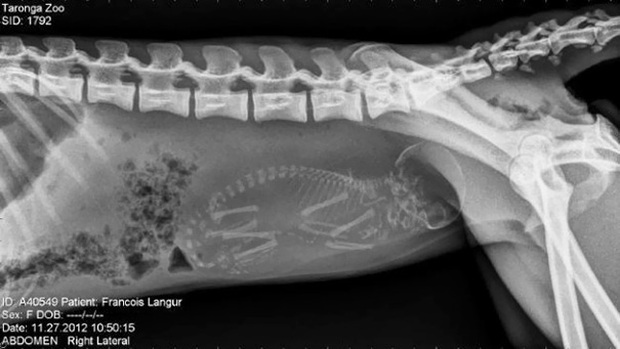

Hình ảnh trông kỳ lạ và cực khó đoán như thể một con vật 4 chân nào đó mang thai em bé. Tuy nhiên, đây là ảnh chụp X-quang một con voọc đen má trắng (khỉ Francois) mang thai.

Cận cảnh hình chụp X-quang một cô mèo đang mang thai và loạt ảnh động vật mang bầu khiến người xem rùng mình nhưng rồi thấy đẹp khó tả - Ảnh 2.